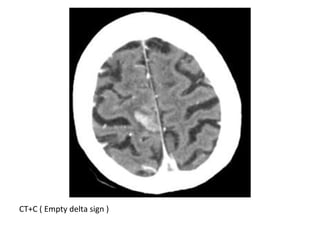

CT+C (Empty delta sign)

CT+C ( Empty delta sign )